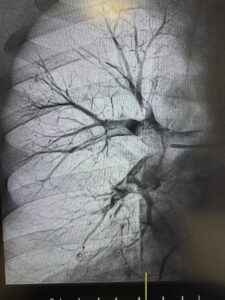

Під рентгенконтролем через судини катетером ми дісталися тромбів й видалили їх спеціальною системою аспірації.

Це перші успішні тромбаспірації при ТЕЛА, виконані у нашому об’єднанні.